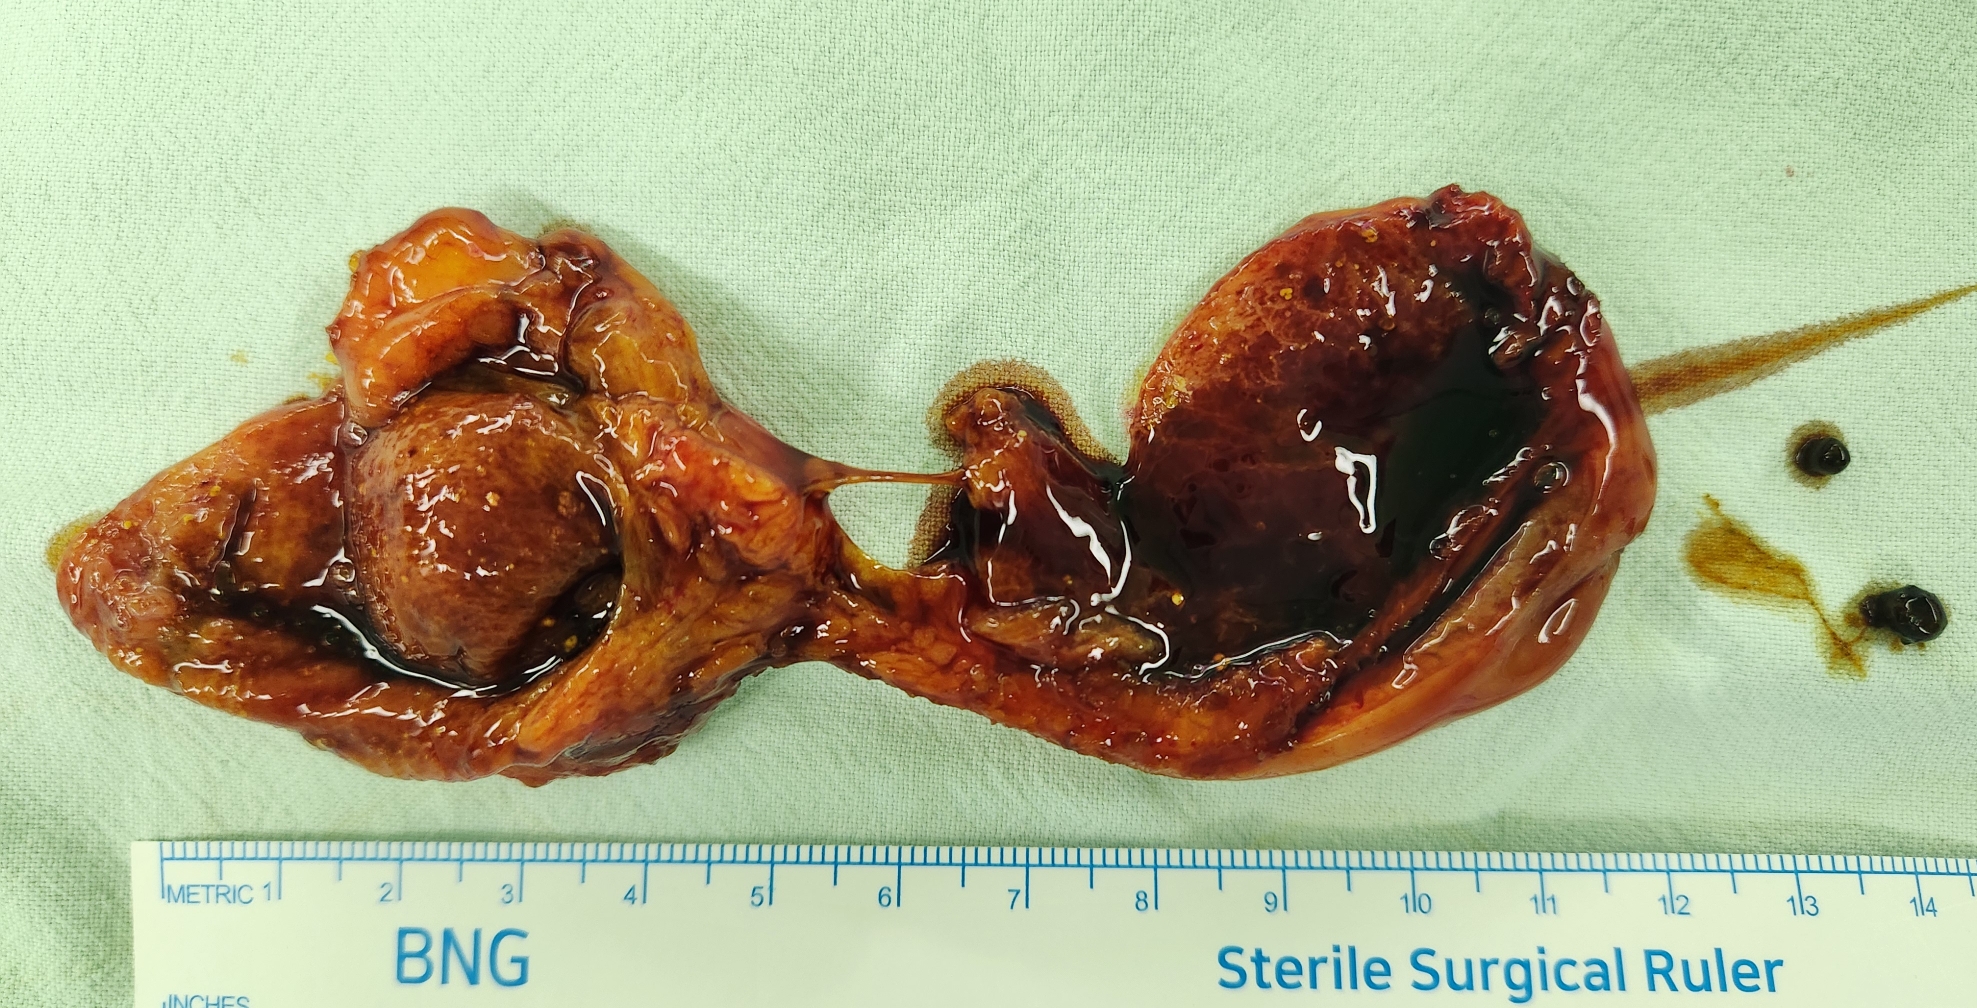

상복부통증으로 본원 응급실에서 담낭관 결석으로 인한 급성 담낭염으로 확인후 제게 수술위해 의뢰된 분입니다.

방금 복강경 담낭절제술을 시행했습니다.